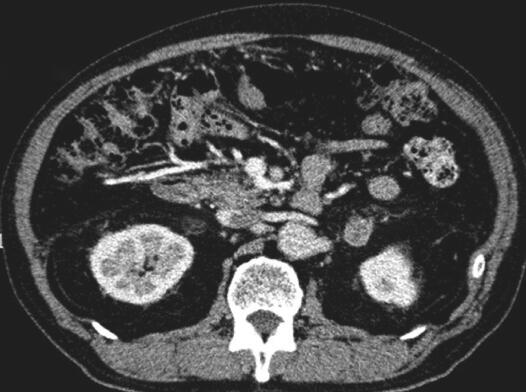

双侧肾上腺CT扫描示:双侧肾上腺区类圆形低密度影,与双侧肾上腺外支分界不清(图1)。双侧肾上腺增强CT扫描:双侧肾上腺区类圆形占位,肿瘤性病变可能:转移瘤?腺瘤?(图2,图3)。

图2 双肾及肾上腺增强CT(轴位):CT示双侧肾上腺腺瘤(箭头标注处)